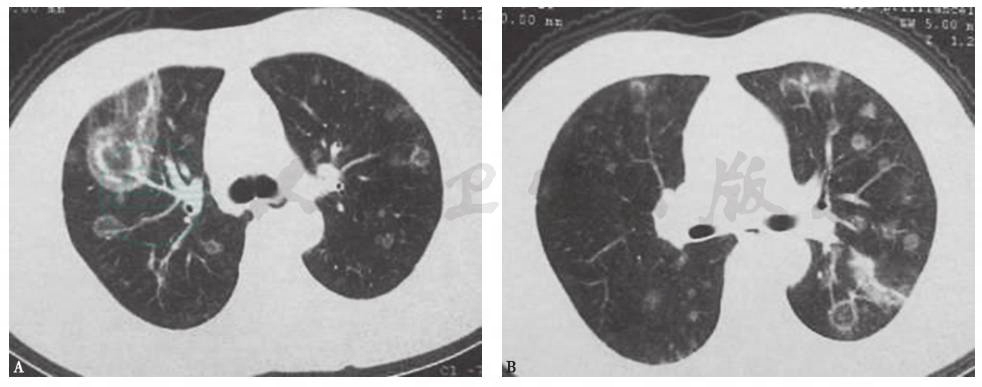

本例患者为老年女性,平时身体健康,无结构性肺病病史,入院前行肠镜检查提示乙状结肠溃疡性浸润性病变,且有明显体重下降表现,不能排除胃肠道肿瘤肺转移的可能。肺转移性肿瘤可分为血行性转移和淋巴性转移,以前者多见。经血行转移时可出现双肺结节样病灶,多为圆形或类圆形,边缘光整,密度均匀,以两中下肺多见(图3)。而本例患者胸部CT表现为不规则结节影,部分可见支气管充气征象,且短期进展迅速,考虑为肺转移性肿瘤可能性不大,但须进一步检查相应临床指标以排除之。

图3 肺转移性腺癌胸部CT表现

男性患者,58岁,咳嗽、咳痰3个月,气喘2个月,诊断为肺转移性腺癌。胸部CT见双肺多发结节性病变,部分空洞形成

图4 侵袭性肺曲霉菌病胸部CT表现

女性患者,35岁,乏力1个月,发热5天,诊断为粒细胞缺乏症合并侵袭性肺曲霉菌病。胸部CT可见双肺多发实变斑片影,多发晕征结节伴新月形空洞形成

图5 肺曲霉菌感染胸部CT表现

女性患者,55岁,间断发热1个月,咳嗽1周,痰中带血1天,诊断为侵袭性肺曲霉菌病。胸部CT可见双肺多发结节影伴反晕征形成